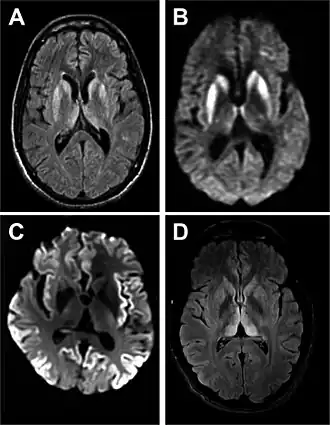

| Ressonância magnética de DCJ esporádica[2] | |

A DCJ é causada por proteínas denominadas priões.[4] Os priões são proteínas mal enoveladas que fazem com que proteínas corretamente enoveladas se tornem elas próprias desenoveladas.[3] Cerca de 85% dos casos ocorrem por razões desconhecidas, enquanto cerca de 7,5% dos casos são herdados de um dos progenitores de forma autossómica dominante.[3][5] A doença pode também ser transmitida por exposição ao cérebro ou tecidos da medula espinal de uma pessoa infetada.[3] Não há evidências de que possa ser transmitida entre pessoas por contacto normal ou transfusão de sangue.[3] O diagnóstico da doença requer que sejam descartadas outras potenciais causas e pode ser complementado por electroencefalograma, punção lombar ou ressonância magnética.[3]